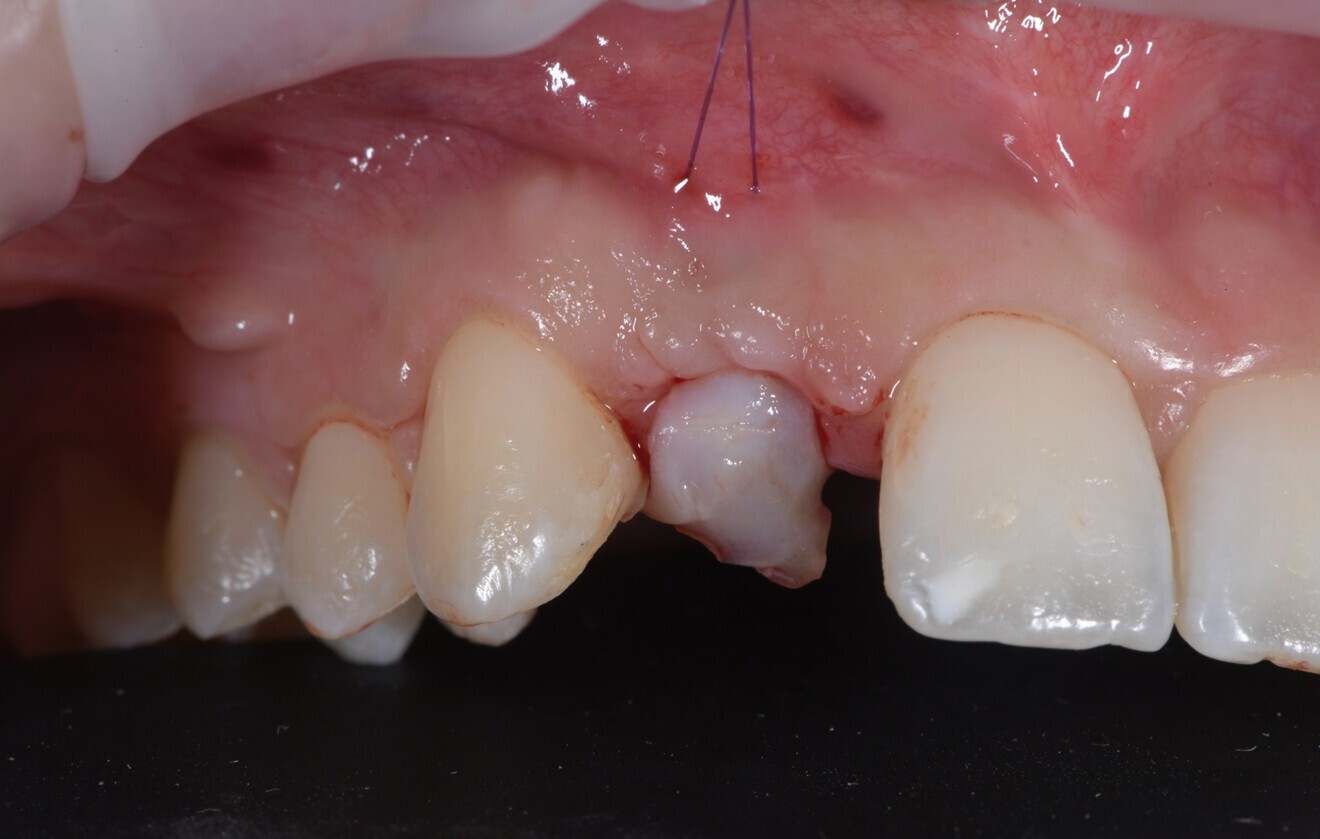

Fig. 1: Peri-implant mucosal inflammation and umbrella effect from bone loss and titanium show-through. (All images: Dr Marco Tallarico)

A 26-year-old partially edentulous female patient was referred to our clinic with an aesthetic concern in the region of the maxillary right lateral incisor. Clinical examination revealed an osseointegrated but malpositioned implant. The peri-implant soft tissue appeared thin and inflamed. Additionally, a dark-greyish discoloration was visible through the gingiva—referred to as the umbrella effect—caused by the loss of peri-implant bone and show-through of the titanium implant (Fig. 1).